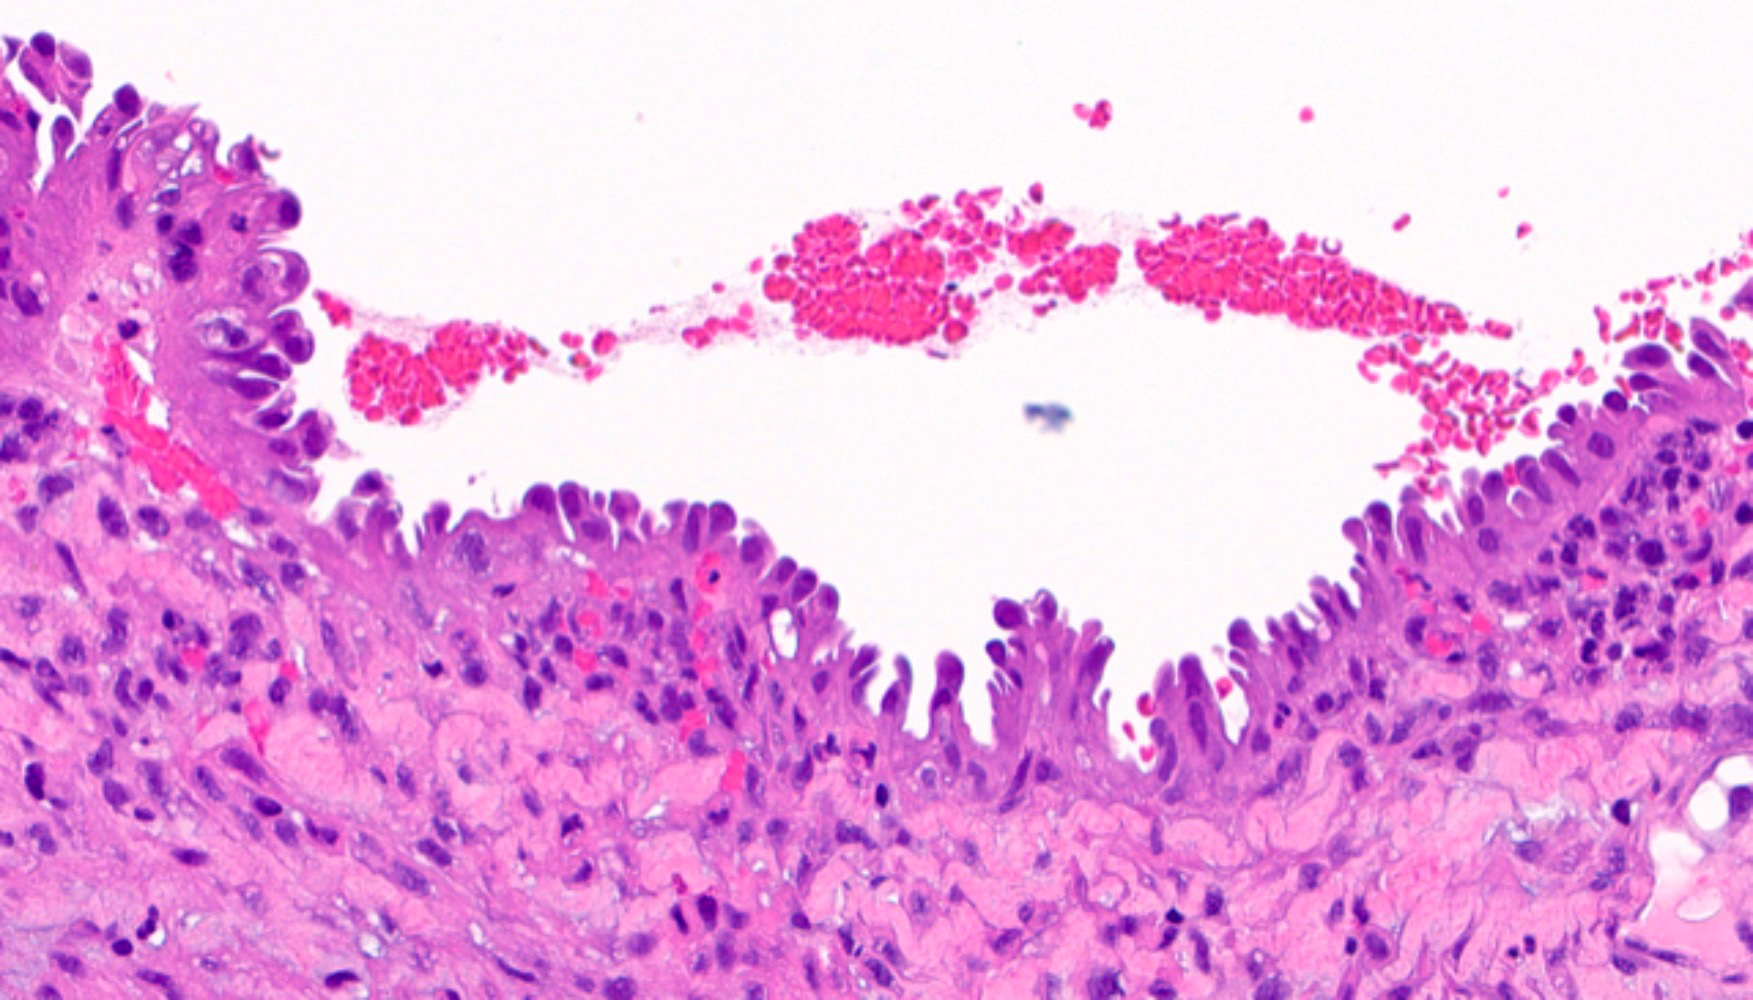

Microscopic (histologic) images

Contributed by Jessica L. Bentz, M.D.

- Papillary metaplasia (Am J Surg Pathol 2013;37:167):

- Papillary syncytial: pseudostratified eosinophilic cells with indistinct cell borders and loss of nuclear polarity (Int J Gynecol Pathol 2012;31:206)

- Sometimes termed as pseudopapillary due to the absence of fibrovascular cores

- Generally located on the surface

- Associated with stromal breakdown

- Tubal metaplasia (Mod Pathol 2011;24:1254):

- Resembling fallopian tube epithelium; pseudostratified with ciliated eosinophilic cells and clear round cells

- Secretory metaplasia:

- Resembling early to late secretory endometrium, with subnuclear to supranuclear vacuolization